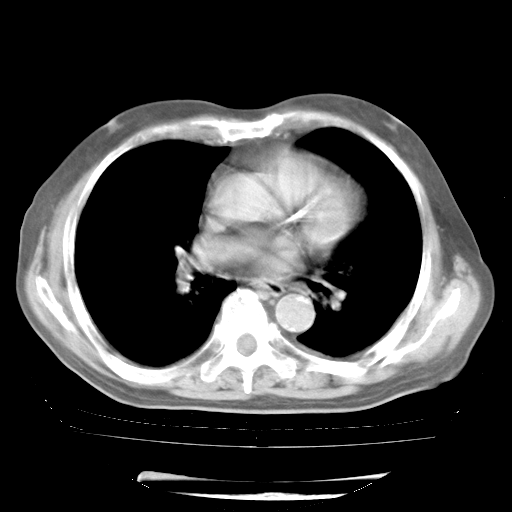

4月28日肺部CT——再次出现类似去年5月9日——透光度降低,“间质性”改变。

4月28日肺部CT——再次出现类似去年5月9日——磨玻璃样、间有“粟粒样”改变。

个人阅读4.14日肺部CT平扫:纵隔窗无异常,但肺窗示:双下肺内、后基底段有片絮状侵润影,部位以后基底段为著,以间质改变为主,呈急性肺泡炎征像,和首次住院影像学有相似之处。仅是个人读片,明日请相关专家再读片哈。其它建议同上。

1、108#的是4月14日的胸部CT(发此贴时还没看着28日的CT)。14日的胸部CT其实已经出现改变(如108#所述),个人认为28日的胸部CT除纵膈窗疑似有双侧胸膜增厚或少量胸积液(可行胸部B超明确)外,与4月14日对照病变有所加重;2、已经给予“异烟肼、利福平、乙胺丁醇”抗痨治疗?如果是,甲强龙80mg可缓慢减量;如果环磷酰胺已停用,暂不使用;3、中性粒细胞92%,明显升高,目前体温情况?注意合并细菌感染可能,使用左氧氟沙星情况下,是否联用B-内酰胺类抗菌药物?另外是查免疫全套非风湿全套。

今请临免主任会诊后认为:4月14日胸部CT已有双下肺间质性改变。患者病情复发多系激素减量过快不正规所致。目前甲强龙80mg/日,一周后酌情开始减量,不易过快。环磷酰胺若已停用,暂不使用。他同意目前抗菌药物使用,但应考虑是否加用B-内酰胺类抗菌药物(中性细胞明显增高);2、结核复发目前依据不足;3、若免疫全套各项指标正常,考虑多系特发性肺间质炎可能大。4、加强支持,并注意保护胃黏膜。

今上午去请教了临免、呼吸主任:1、介绍病史和阅读系列胸部CT一致认为:患者肺结核不考虑,仍为肺间质纤维化,目前处于急性肺泡炎阶段。2、若仍发热,可将甲强龙增至:80mg Bid静滴,同时鉴于中性增高,合并细菌感染可能,继续左氧氟沙星治疗,再联用B-内酰胺抗菌药物,如头孢哌酮--舒巴坦;3、停用抗痨药;4、目前甲强龙每日剂量160mg ,体温正常后再酌情减量;目前暂不用免疫抑制剂;4、不建议使用免疫增强剂等;5、加强支持治疗,鼓励患者进食;5、注意随访肝、肾功及血常规情况;6、因患者目前激素用量较大,加用胃黏膜保护剂,防止消化道出血可能。